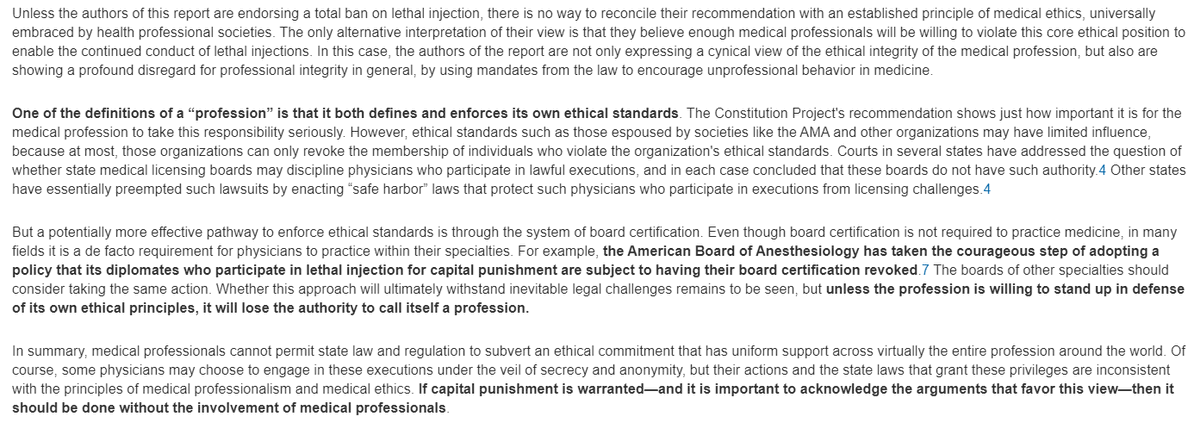

Some vilify the death penalty for a few criminals condemned publicly in a court of law

but defend destruction of millions of unborn children as a private issue 2 b decided between a woman & her abortionist

Some vilify the death penalty for a few criminals condemned publicly in a court of law

but defend destruction of millions of unborn children as a private issue 2 b decided between a woman & her abortionist

7. The tried & condemned will, before a crowd of somber witnesses, receive anesth b4 lethal inject'n, time of death recorded, body receiving a resp'ful burial.

Unborn child gets no anesthesia before being quietly dismembered in her mother's womb, her tiny parts heaped on a tray

Unborn child gets no anesthesia before being quietly dismembered in her mother's womb, her tiny parts heaped on a tray

8. This is unconscionable, indefensible, outrageous barbarity.